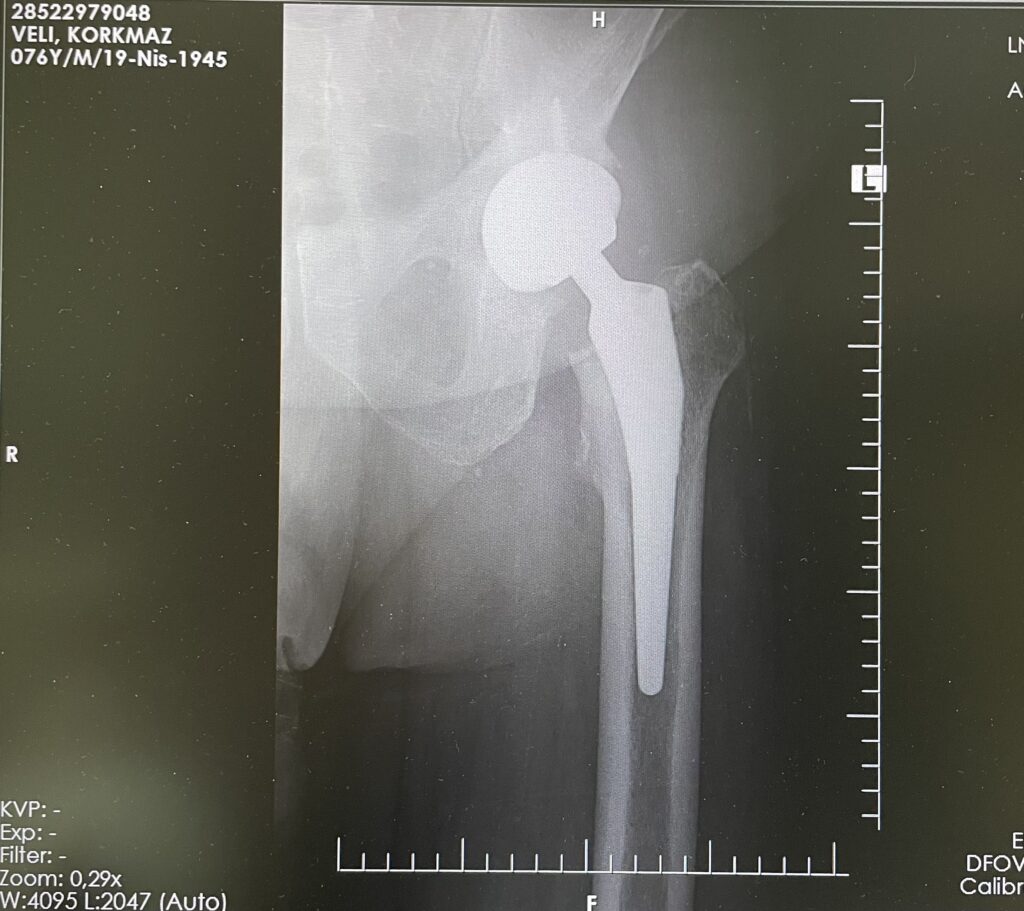

V.K.